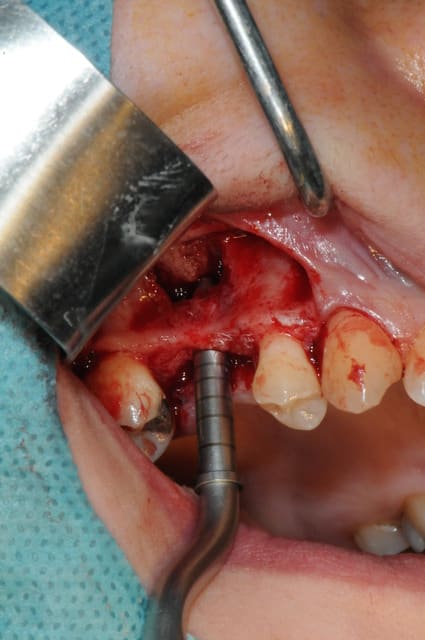

je sais pas si c'est un produit miracle, mais pour les sinus lift, c'est fantastique.

outre le fait de stabiliser un implant dans un sinus type SA4, pas de risque de voir partir le produit comme avec les granules de bioos et autres..

l'autre avantage est de ne pas avoir à mettre de membrane de recouvrement.

je suis donc hyper satisfait du résultat.

jugez plutôt...

l'application type du VitalOs, avec le bone splitting.

le protocole tel qu'il est d'écrit voudrait que l'on applique d'abord une couche de vital os en palatin - laisser durcir - mettre l'implant puis mettre une dernière couche.

ici, j'ai mis l'implant- maintenu la membrane de Schneider en poussant avec l'embout sur celle ci et terminer l'injection du produit. c'est l'un des avantages de ce produit, il est livré avec deux embouts donc les deux solutions sont possibles pour une même seringue.